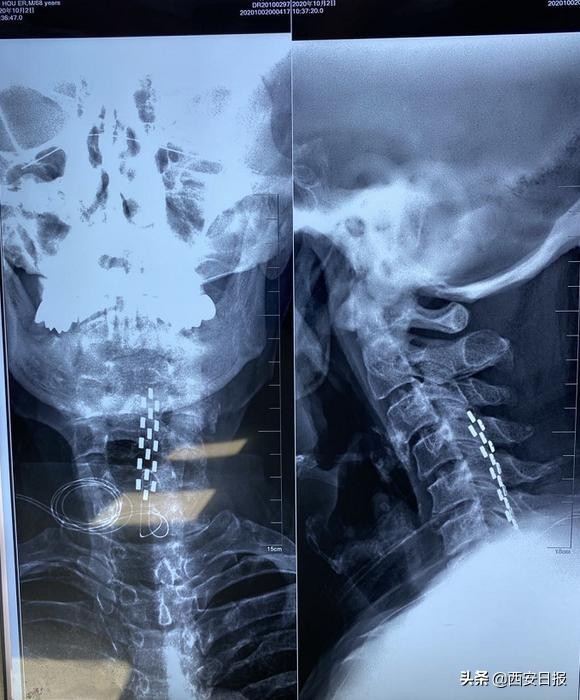

陈伟副教授根据患者病情分析患者疼痛可能跟1年前进行的脊髓神经电刺激有关,需要评估是否电极有移位。如果各种止痛治疗没有效果,可以评估鞘内镇痛泵植入评估,术前测试根据单次注射*啡吗**止痛效果判断患者是否适合这一疗法。随后,西安交大一附院神经外科功能组王茂德副院长、陈伟副教授专家团队为杜先生制定个体化治疗方案。经过一系列严谨的术前检查,以及详尽的术前方案设计后,10月22日,王茂德教授、陈伟副教授专家组成功为杜先生进行鞘内药物输注泵植入手术,在术后第一天,患者睡了十几年来第一个安稳觉。